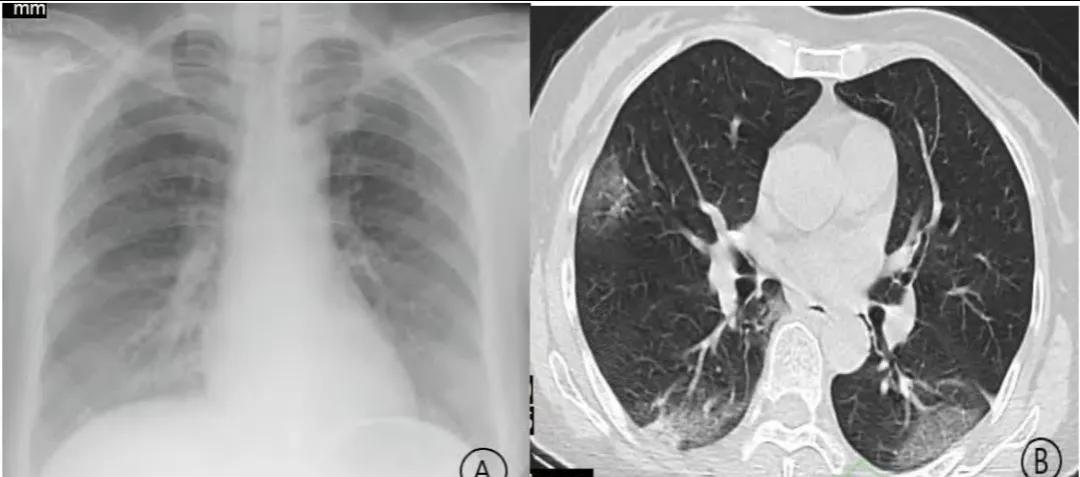

白肺的CT图片